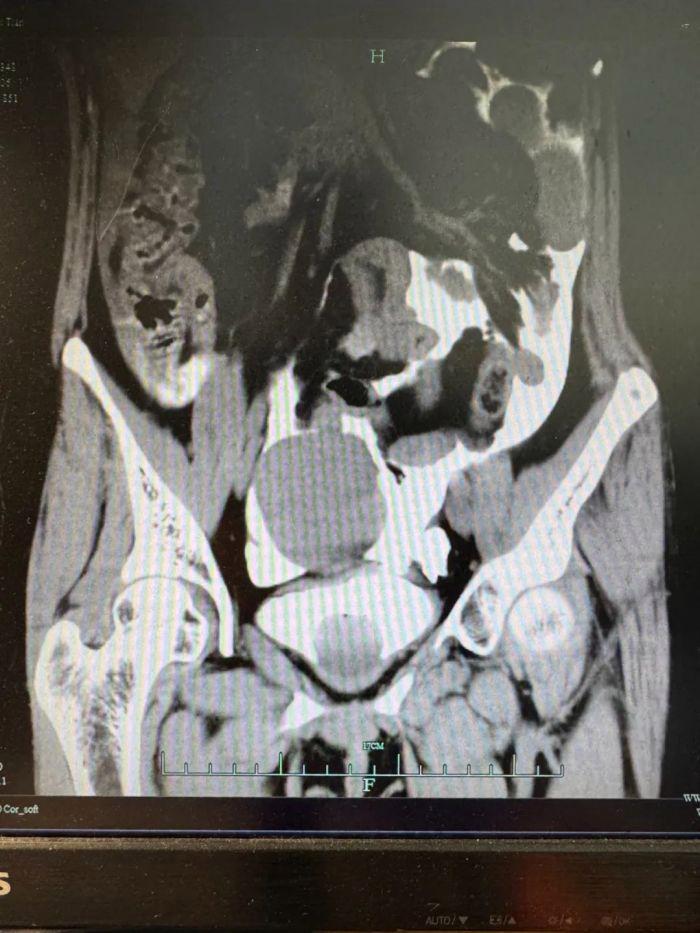

经超声和CT检查显示,小李的腹腔内有大量的液体,腹腔穿刺吸出淡红色血性液体。

患者CT影像

“立刻安排膀胱造影!病人很可能膀胱破了!”泌尿外科秦勇主任紧急会诊后,认为病人虽无明显腹部外伤痕迹,但根据病史描述及症状表现判断膀胱破裂可能性较大。随后的CT膀胱造影检查结果证实了秦主任的判断,同时也让所有人倒吸冷气:膀胱真的破了,腹腔里积存了十几个小时的尿液!